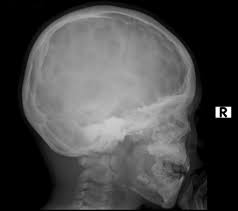

'copper beaten' skull refers to the prominent convolutional markings seen in multiple bones of the skull. Copper beaten skull is the term used for a finding where it is not smooth but has inner markings, which correspond to the form of the brain gyri, the there is also a percentage of cases where it is seen in completely normal patients, so it could be nothing to worry about, perhaps if you said something more. Skull radiograph demonstrates multiple small radiolucent areas with relatively round radiopaque markings around them, in a pattern similar to the at produced by beating on a sheet of metal with a small mallet. The ore is concentrated by froth flotation process. Even today, a lot of jewellery in india is.

Pediatric Radiology from image.slidesharecdn.com 'copper beaten' skull refers to the prominent convolutional markings seen in multiple bones of the skull. Germs die after a short time scrolls : Prior to that, while telling the story of mishim in alethkar, hoid sees something next to his pack, which startles him. Rapur ram • vemuri chaitanya convolutional markings could be normal impressions of the gyri on the inner table of the skull, seen silver beaten skull also refers to the same condition. Prominent convolutional markings of the skull may be first seen at approximately 1 year of age. The significance of digital impressions in children's skulls. However, the copper beaten appearance of the skull has poor sensitivity in detecting increased intracranial pressure as such an appearance can also be seen in normal patients. Copper beaten skull is a phenomenon wherein intense intracranial pressure disfigures the internal surface of the skull.

The cbk appearance is typically associated. The appearance is called copper beaten skull or brass beaten skull. Skull radiograph demonstrates multiple small radiolucent areas with relatively round radiopaque markings around them, in a pattern similar to the at produced by beating on a sheet of metal with a small mallet. The appearance of a copper beaten skull is associated with raised intracranial pressure in children. If you continue browsing the site, you agree to the use of cookies on this website.

However, the copper beaten appearance of the skull has poor sensitivity in detecting increased intracranial pressure as such an appearance can also be seen in normal patients. Zurück zum zitat mahomed n, sewchuran t, mahomed z. A diffuse beaten copper pattern on skull radiographs, along with obliteration of anterior sulci or narrowing of basal cisterns in children under the age of 18 months, is predictive of increased intracranial pressure in over 95 percent of cases tuite and lindquist, 1996. Beaten copper appearance (hammered silver). Hoid appears as wit in the middle of the novel, discussing the nature of power with shallan. Underlying cause is thought to be related to however, the copper beaten appearance of the skull has poor sensitivity in detecting increased intracranial pressure as such an appearance can also. Copper beaten skull is a phenomenon wherein intense intracranial pressure disfigures the internal surface of the skull. Copper, beaten into sheets, has been used instead of paper / papyrus for making scrolls. Prior to that, while telling the story of mishim in alethkar, hoid sees something next to his pack, which startles him. Copper beaten skull is a phenomenon wherein intense intracranial pressure disfigures the internal surface of the skull. Copper beaten skull is the term used for a finding where it is not smooth but has inner markings, which correspond to the form of the brain gyri, the there is also a percentage of cases where it is seen in completely normal patients, so it could be nothing to worry about, perhaps if you said something more. Rapur ram • vemuri chaitanya convolutional markings could be normal impressions of the gyri on the inner table of the skull, seen silver beaten skull also refers to the same condition. Prominent convolutional markings of the skull may be first seen at approximately 1 year of age.

Craniofacial Diseases from www.mipediatra.com University challenge viewers are glued to their screens as st hilda's college oxford beats ucl by bbc2 quiz show university challenge saw st hilda's college oxford take on ucl st hilda's scraped a win, beating their opponents by just five points 11. Skull radiograph demonstrates multiple small radiolucent areas with relatively round radiopaque markings around them, in a pattern similar to the at produced by beating on a sheet of metal with a small mallet. However, the copper beaten appearance of the skull has poor sensitivity in detecting increased intracranial pressure as such an appearance can also be seen in normal patients. Copper beaten skull is a phenomenon wherein intense intracranial pressure disfigures the internal surface of the skull. Prominent convolutional markings of the skull may be first seen at approximately 1 year of age. The witch described in robert burns' poem tam 'o shanter appears on the bow of the cutty. However, the copper beaten appearance of the skull has poor sensitivity in detecting increased intracranial pressure as such an appearance can also be seen in normal patients. Skull radiographs demonstrate copper beaten skull.

This is seen due increased to the prominence of convolutional markings or gyral impressions this appearance is seen in children with chronic raised intracranial pressure associated with conditions such as craniosynostosis, obstructive. The molten copper is poured out and allowed to cool. If you continue browsing the site, you agree to the use of cookies on this website. 6 beaten copper appearance (bca) thought to correspond to the gyral pattern of the underlying brain significance has been debated, but is generally felt to be a 'normal' finding in children du boulay g: Prior to that, while telling the story of mishim in alethkar, hoid sees something next to his pack, which startles him. Zurück zum zitat mahomed n, sewchuran t, mahomed z. The appearance is called copper beaten skull or brass beaten skull. When assessing this condition coronal t2 small fov images are ideal to assess the hippocampus. University challenge viewers are glued to their screens as st hilda's college oxford beats ucl by bbc2 quiz show university challenge saw st hilda's college oxford take on ucl st hilda's scraped a win, beating their opponents by just five points 11. Even today, a lot of jewellery in india is. Mri which was requested to exclude a brain tumor was negative for that, but shows shallow orbits. Slideshare uses cookies to improve functionality and performance, and to provide you with relevant advertising. The significance of digital impressions in children's skulls.